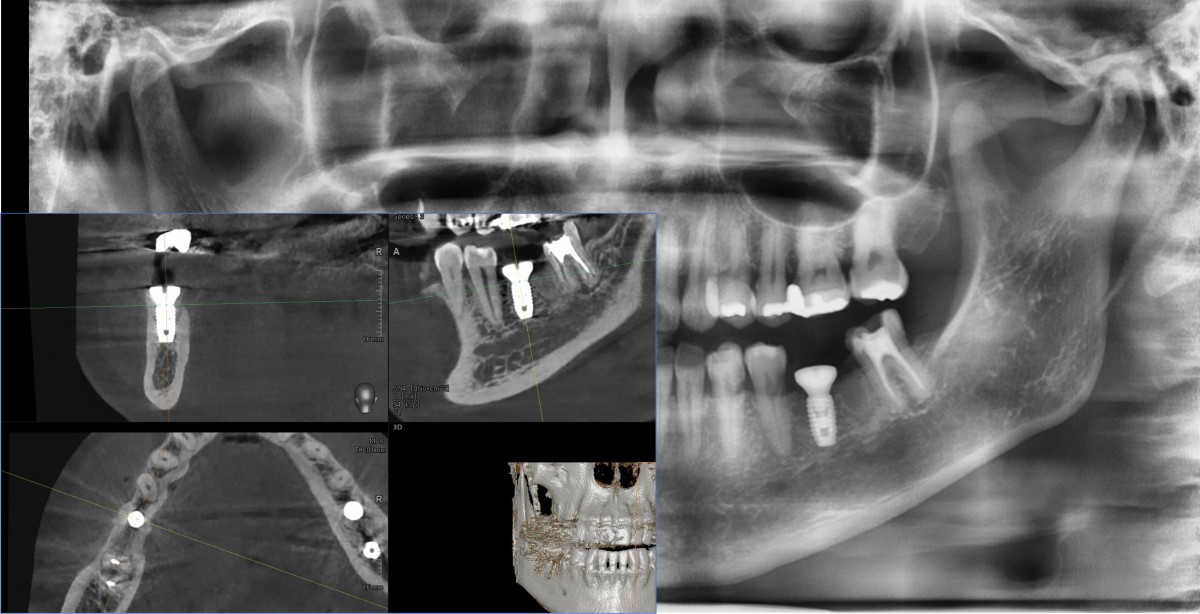

Immediate placement of an implant (Arum Dnetistry NB1, 5*8.5)

A 51-year-old patient complained of an

old-crowned molar. The lower left molar had a gold crown, and the margin showed discoloration indicative of inner caries. Also, it had furcation-involved periodontitis

with an apical lesion.

Extraction and immediate placement of an implant.

▲Arum Dentistry NB1 fixture (5*8.5mm)